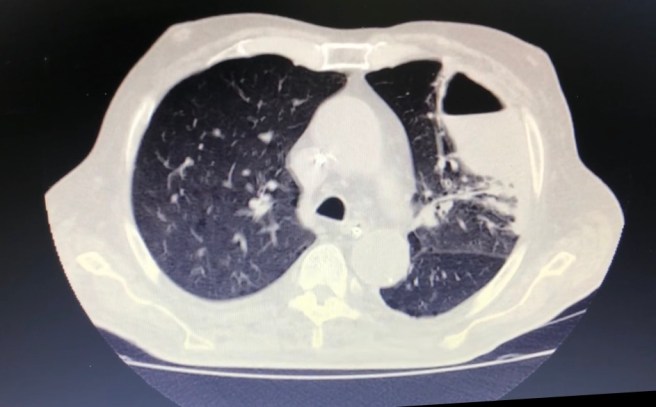

Imagem: abcesso pulmonar 5 de dezembro de 2018 ~ infectologia em geral Compartilhe isso: Compartilhar no X(abre em nova janela) 18+ Compartilhar no Facebook(abre em nova janela) Facebook Envie um link por e-mail para um amigo(abre em nova janela) E-mail Imprimir(abre em nova janela) Imprimir Curtir Carregando... Relacionado